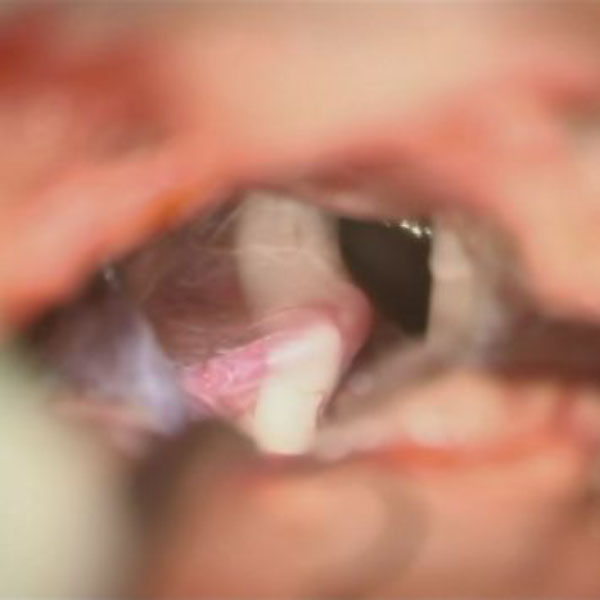

580

兵庫県の病院

'26年2月

70代

右三叉神経痛

減圧前